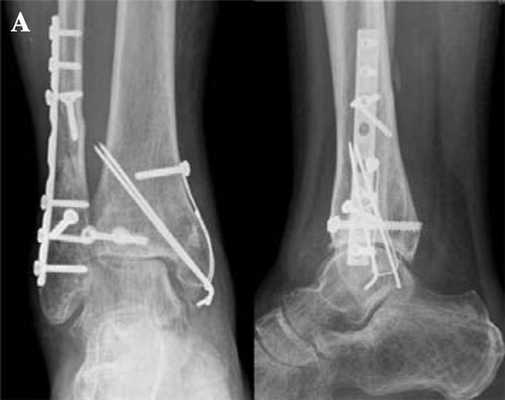

Как проходит операция

Эндопротезирование проводят под общим или местным наркозом. Пациент лежит на спине. Ногу перетягивают манжетой, чтобы предотвратить поступление крови (если операция будет затяжной). Для получения моментального изображения хирург использует мобильный рентгеновский аппарат под стерильным покрытием, что позволяет контролировать ход операции и локализацию протеза.

- С помощью рентген-аппарата и специальных инструментов определяют ось и положение заднего отдела стопы для имплантации.

- Таранную кость покрывают металлическим колпачком (внутри него есть металлические штифты, позволяющие совершать движения).

- Поверхность сустава большеберцовой кости покрывают защитной металлической пластинкой, оба компонента также покрывают специальным слоем для надежного сращивания костной ткани.

- Устанавливают подвижное скользящее ядро.